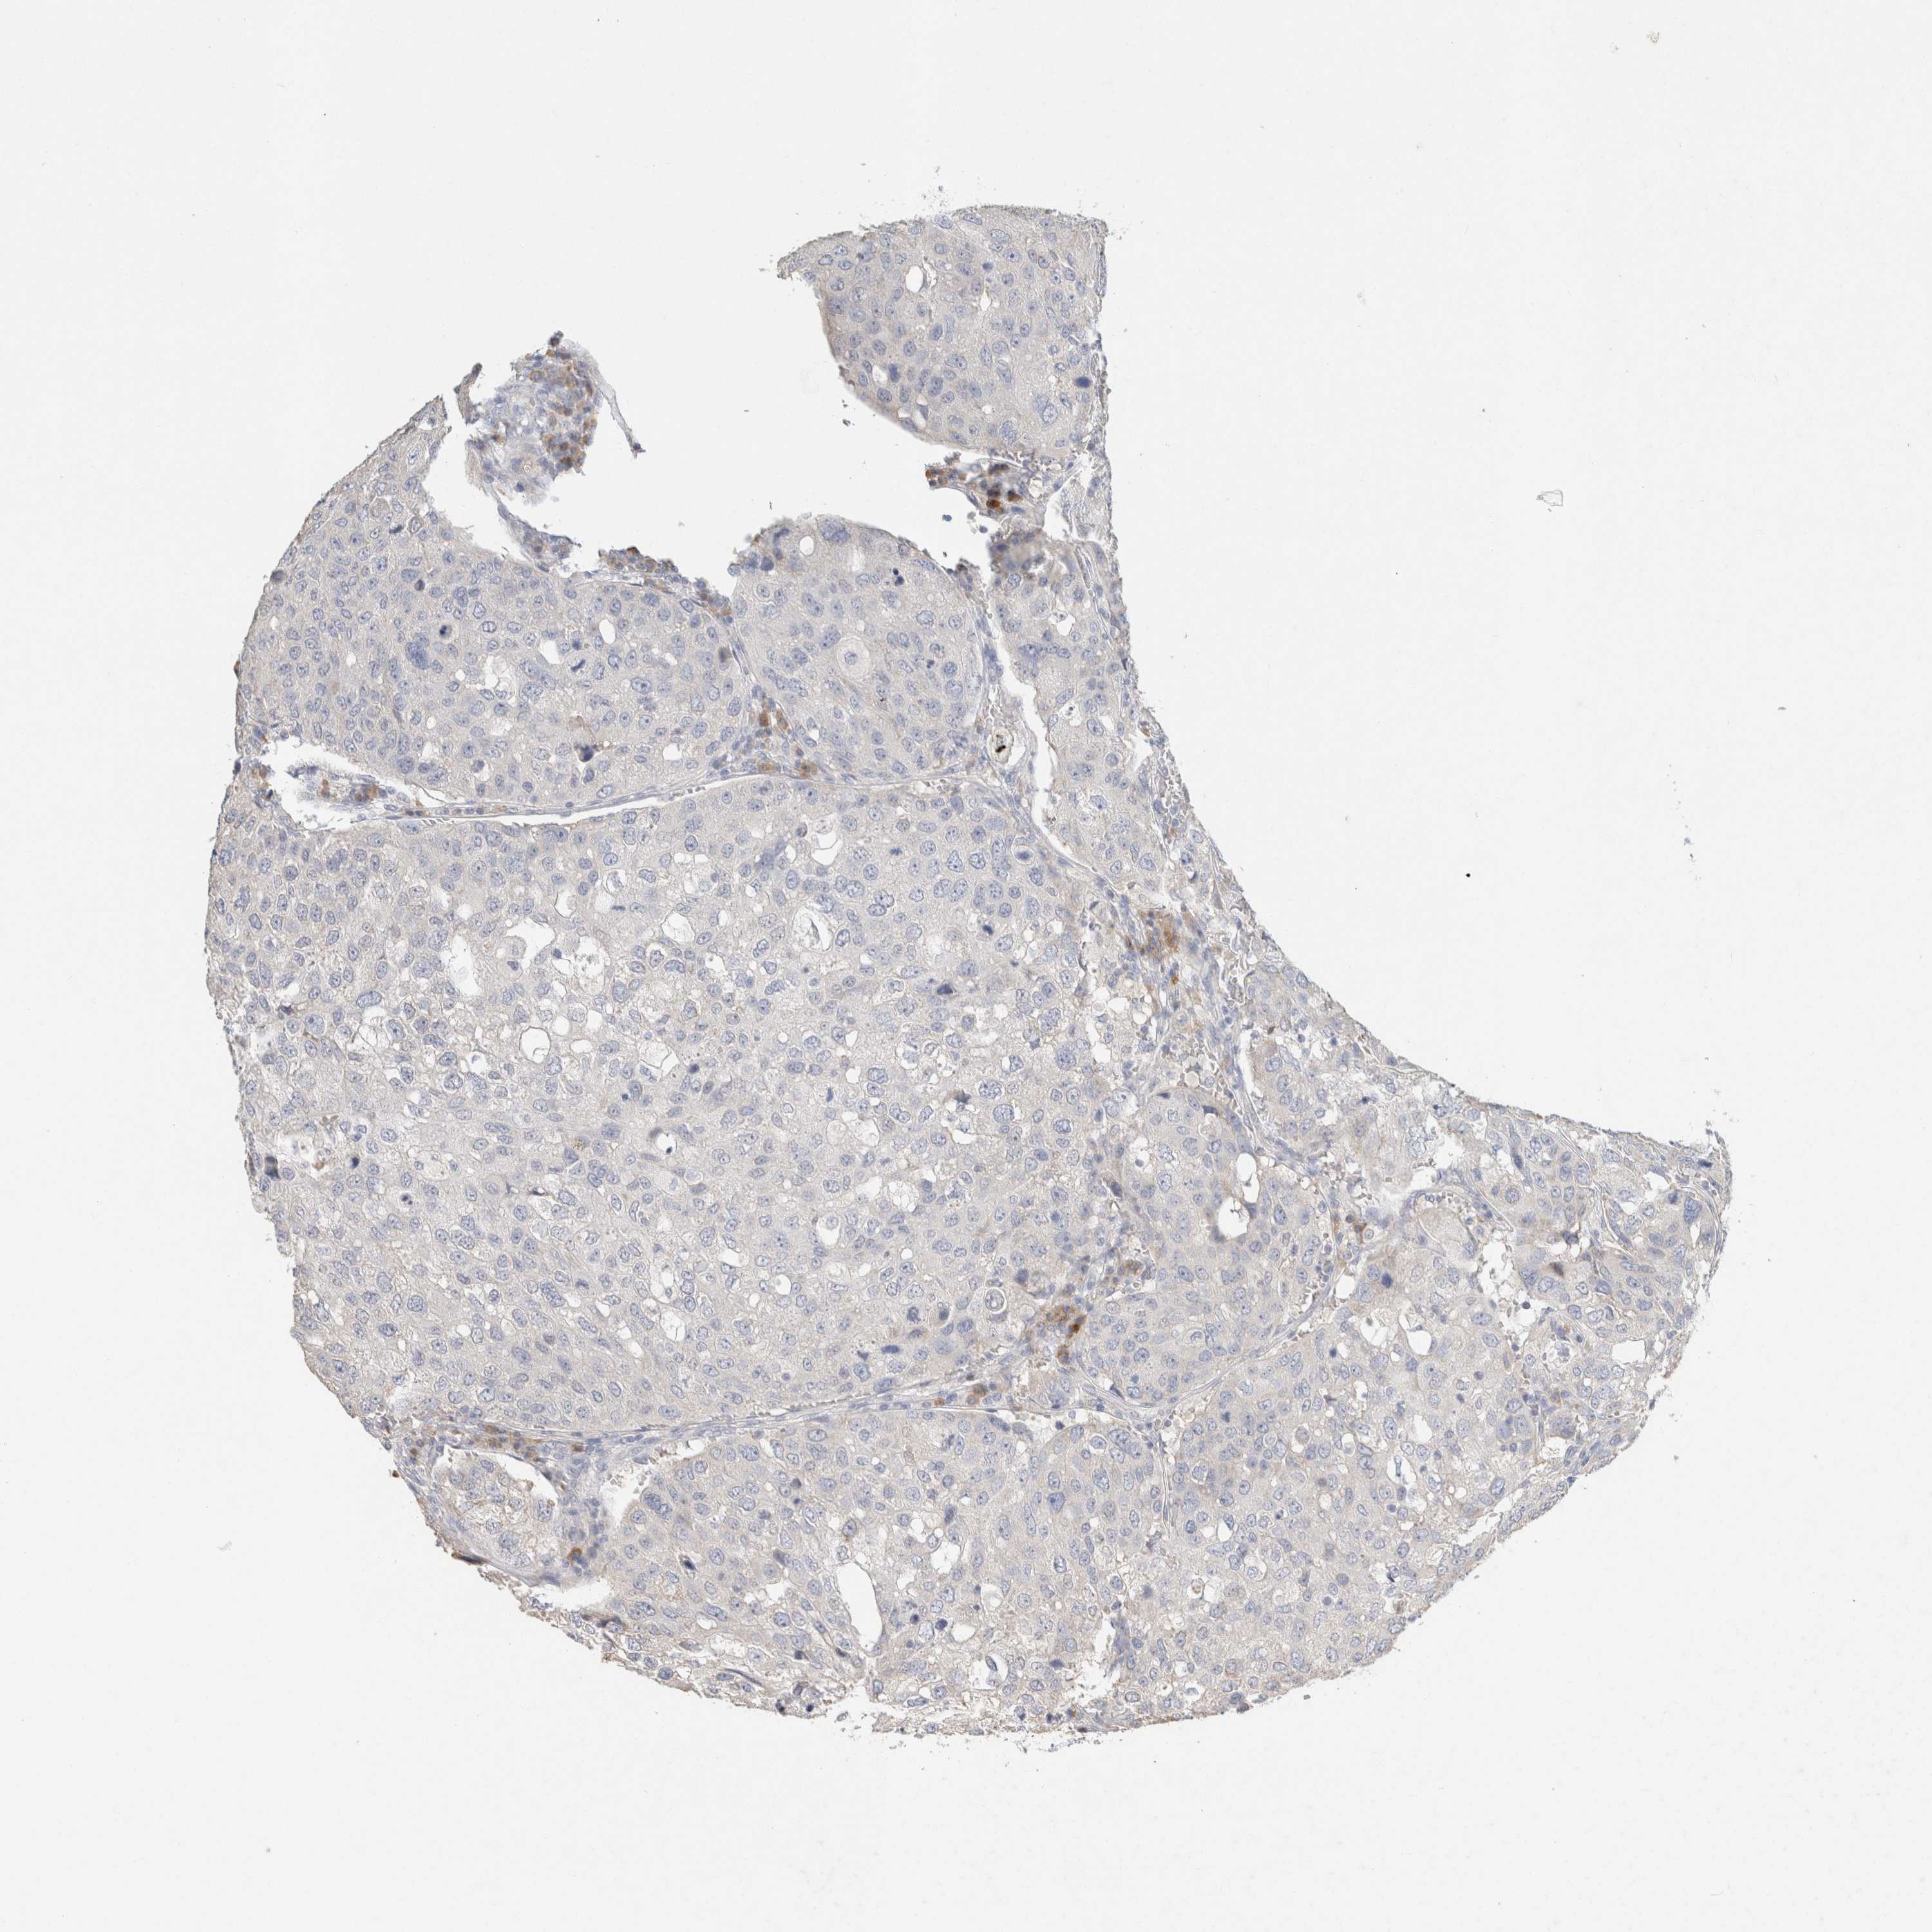

UROTHELIAL CANCER - Protein expressioni

A mouse-over function shows sample information and annotation data. Click on an image to view it in a full screen mode. Samples can be filtered based on level of antibody staining by selecting one or several of the following categories: high, medium, low and not detected. The assay and annotation is described here.

Note that samples used for immunohistochemistry by the Human Protein Atlas do not correspond to samples in the TCGA dataset.

Antibody stainingi

Antibody staining in the annotated cell types in the current human tissue is reported as not detected, low, medium, or high, based on conventional immunohistochemistry profiling in selected tissues. This score is based on the combination of the staining intensity and fraction of stained cells.

Each image is clickable and will lead to virtual microscopy that enables deeper exploration of all samples and also displays staining intensity scores, fraction scores and subcellular localization as well as patient and tissue information for each sample.

Antibody HPA022845

Antibody HPA023138

Antibody CAB010900

Antibody CAB012976

Urothelial carcinoma, Low grade

Urothelial carcinoma, High grade